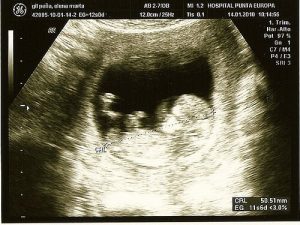

Ultralyd:

Det er en helt almindelig procedure, som er god til både at opdage problemer samt få det første billede af babyen.

Denne procedure gør det muligt for parret at finde ud af barnets køn. Det giver også mulighed for påvisning af tidligere anomalier som hjertefejl og kromosomale ændringer.

Ultralyd på andet test stadie, anbefales for nøje at observere de mulige defekter, som fosteret kan frembringe. Ultralyd på andet stadie anbefales, når screeningtesten indikerer mulige anomalier.

Det er en ikke-invasiv teknik, der opnås gennem et apparat, der giver et billede ved hjælp af bølger. Bølgerne gør ikke barnet ondt, og giver mulighed for observation af livmoderen.